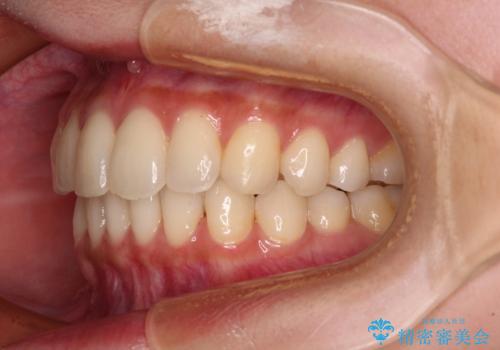

- 前歯のデコボコと強い咬みしめを気にして来院された患者様です。

インビザラインを用いて、前歯の叢生を解消するとともに、ディープバイトを改善していくこととしました。

海外へ転居する予定があったため、1日22時間以上の装着時間をしっかりと守っていただき、予定期間よりも早く、思っていた以上にきれいに仕上げることができました。